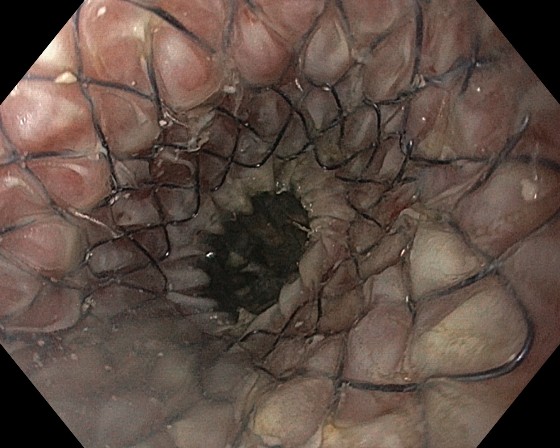

La examenul de fibroesofagoscopie, a fost depistată o compresie a 1/3 inferioară a esofagului cu stenozare pronunţată a lumenului (0,5 cm în diametru). Pe data de 8 decembrie curent s-a efectuat plasarea endoscopică a stentului metalic autoexpandabil cu valvula antireflux în regiunea structurii esofagiene.